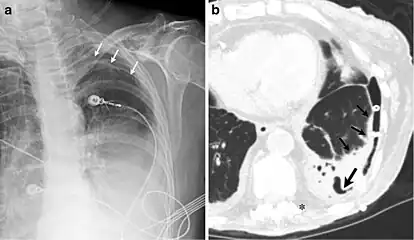

A fibrothorax can typically be diagnosed by taking an appropriate medical history in combination with the use of appropriate imaging techniques such as a plain chest X-ray or CT scan.[1] These imaging techniques can detect fibrothorax and pleural thickening that surround the lungs.[11] The presence of a thickened peel with or without calcification are common features of fibrothorax when imaged.[1] CT scans can more readily differentiate whether pleural thickening is due to extra fat deposition or true pleural thickening than X-rays.[1]

If a fibrothorax is severe, the thickening may restrict the lung on the affected side causing a loss of lung volume.[11] Additionally, the mediastinum may be physically shifted toward the affected side.[1] A reduction in the size of one side of the chest (hemithorax) on an X-ray or CT scan of the chest suggests chronic scarring.[9] Signs of the underlying disease causing the fibrothorax are also occasionally seen on the X-ray.[9] A CT scan may show features similar to those seen on a plain X-ray.[11] Lung function testing typically demonstrates findings consistent with restrictive lung disease.[9]

CXR of an individual affected by fibrothorax (consequence of tuberculosis) -

Extensive left-sided fibrothorax -

Chest radiograph displaying inhomogeneous opacification of the left half of the chest that is fibrothorax -